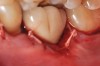

Clinical examination showed 2 mm of buccal recession with a shallow vestibule and absence of keratinized attached gingiva against the crown with 8 mm of circumferential pocketing accompanied by bleeding upon probing (Figure 15 and Figure 16). A periapical radiograph showed a symmetrical vertical osseous defect causing the loss of 50% of the bone around the implant (Figure 17). Because the patient had made a significant investment of time and finances to replace her lost tooth with the implant, she desired that the implant and restoration be retained, if feasible.

Fig 15. The implant-supported restoration of tooth No. 19 presented with a lack of attached keratinized gingiva, shallow buccal vestibule, and 2 mm of buccal recession.

Fig 16. The restoration exhibited an 8-mm pocket upon probing, with bleeding on the buccal aspect.